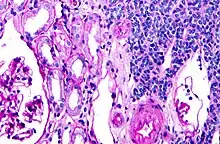

| Micrograph of a metanephric adenoma with structures reminiscent of those seen in papillary renal cell carcinoma. H&E stain. | |

Metanephric adenoma (MA) is a rare, benign tumour of the kidney, that can have a microscopic appearance similar to a nephroblastoma (Wilms tumours),[1] or a papillary renal cell carcinoma.

Metanephric adenoma is diagnosed histologically. The tumours can be located at upper pole, lower pole and mid-hilar region of the kidney; they are well circumscribed but unencapsulated, tan pink, with possible cystic and hemorrhagic foci. They show a uniform architecture of closely packed acinar or tubular structures of mature and bland appearance with scanty interposed stroma.[3][4][5][6][7] Cells are small with dark staining nuclei and inconspicuous nucleoli. Blastema is absent whereas calcospherites may be present. Glomeruloid figures are a striking finding, reminiscent of early fetal metenephric tissue. The lumen of the acini may contain otherwise epithelial infoldings or fibrillary material but it is quite often empty. Mitoses are conspicuously absent.[3][4][5][6][7] In the series reported by Jones et al. tumour cells were reactive for Leu7 in 3 cases of 5, to vimentine in 4 of 6, to cytocheratin in 2 of 6, to epithelial membrane antigen in 1 of 6 cases and muscle specific antigen in 1 of 6.[5] Olgac et al. found that intense and diffuse immunoreactivity for alpha-methylacyl-CoA racemase (AMACR) is useful in differentiating renal cell carcinoma from MA but a panel including AMACR, CK7 and CD57 is better in this differential diagnosis.[8] Differential diagnosis may be quite difficult indeed as exemplified by the three malignancies initially diagnosed as MA that later metastasized, in the report by Pins et al.[9]